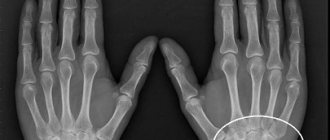

Due to changes in the brain and spinal cord, gradual muscle atrophy and drying occurs. At first you might think that the person has simply lost a lot of weight, but the reason lies in a serious illness. Ultimately, loss of motor function and disability occurs. This violation occurs with various pathologies in the patient’s body. In this case, the muscle tissue dries out and is replaced with connective tissue, which in turn cannot contract.

The muscles in the legs completely atrophy, leading to partial or complete limitation of movement. Very often, weight loss is accompanied by the presence of helminthic parasites. While in the body, they release toxic substances, products of their vital activity, under the influence of which the cellular structure is damaged and food ceases to be absorbed.

As a result of pathological changes in the human body, skeletal muscle begins to thin out and become deformed, then it is replaced by connective tissue that is unable to contract, that is, muscle atrophy occurs. As a result, the motor ability of the affected muscle decreases, and with significant degeneration, complete paralysis occurs, the patient loses the ability to move independently. Diseases associated with muscle atrophy, as a rule, are rare congenital genetic diseases that begin to manifest themselves in childhood. At the very beginning of the disease, a characteristic symptom is rapid fatigue in the legs, muscle weakness during prolonged physical activity. The calf muscles are noticeably enlarged. Atrophy usually begins in the proximal muscle groups of the lower extremities closest to the body.